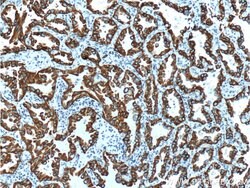

This antibody is specifically against KRT7.

| Immunocytochemistry, Immunofluorescence, Immunohistochemistry (Paraffin), Immunoprecipitation, Western Blot | |